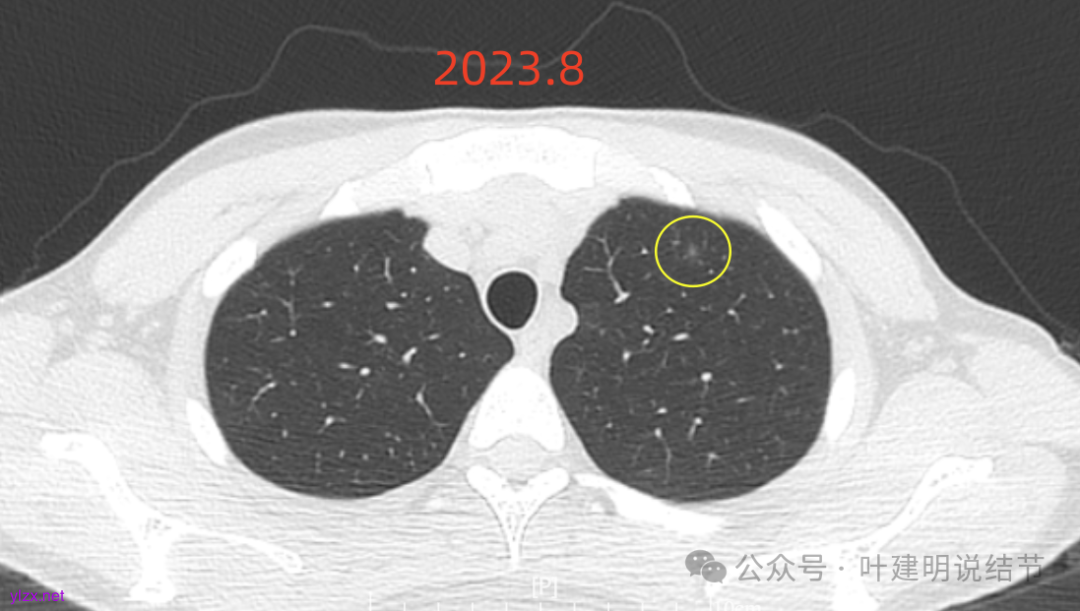

先来看2023年8月的:

病灶6:右下叶脊柱旁囊腔型病灶,整体轮廓与边界清,没有明显实性成分,考虑原位癌或微浸润性腺癌可能性大。